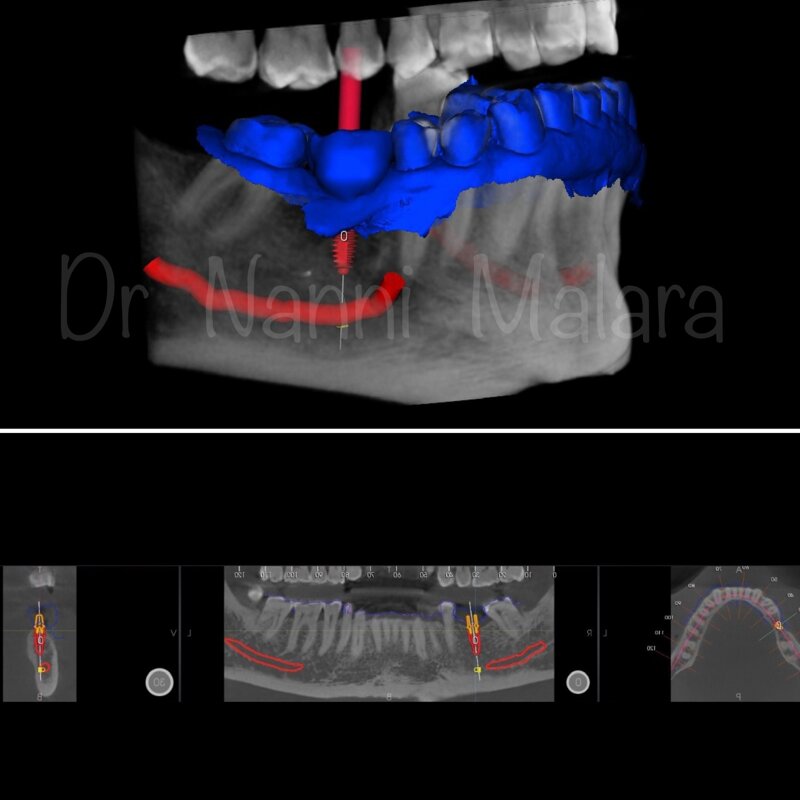

Progettazione con software dedicato

Sito d'intervento : edentulia primo molare inf dx (4.6)